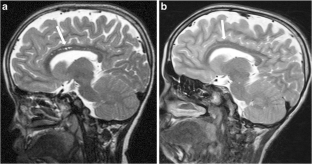

Fig. 2